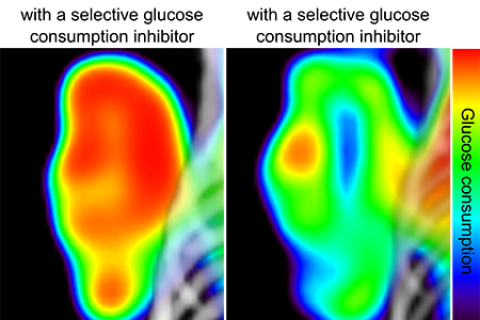

Dr. Peter Clark's lab focuses on the molecular imaging technology positron emission tomography (PET). The lab works on developing new PET imaging probes and assays and tries to understand the relationship between a PET image and the underlying cancer biology. The ultimate goal of the Clark lab is to develop new PET assays to better stratify patients and to predict, on an individual patient level, therapeutic responses to treatments.